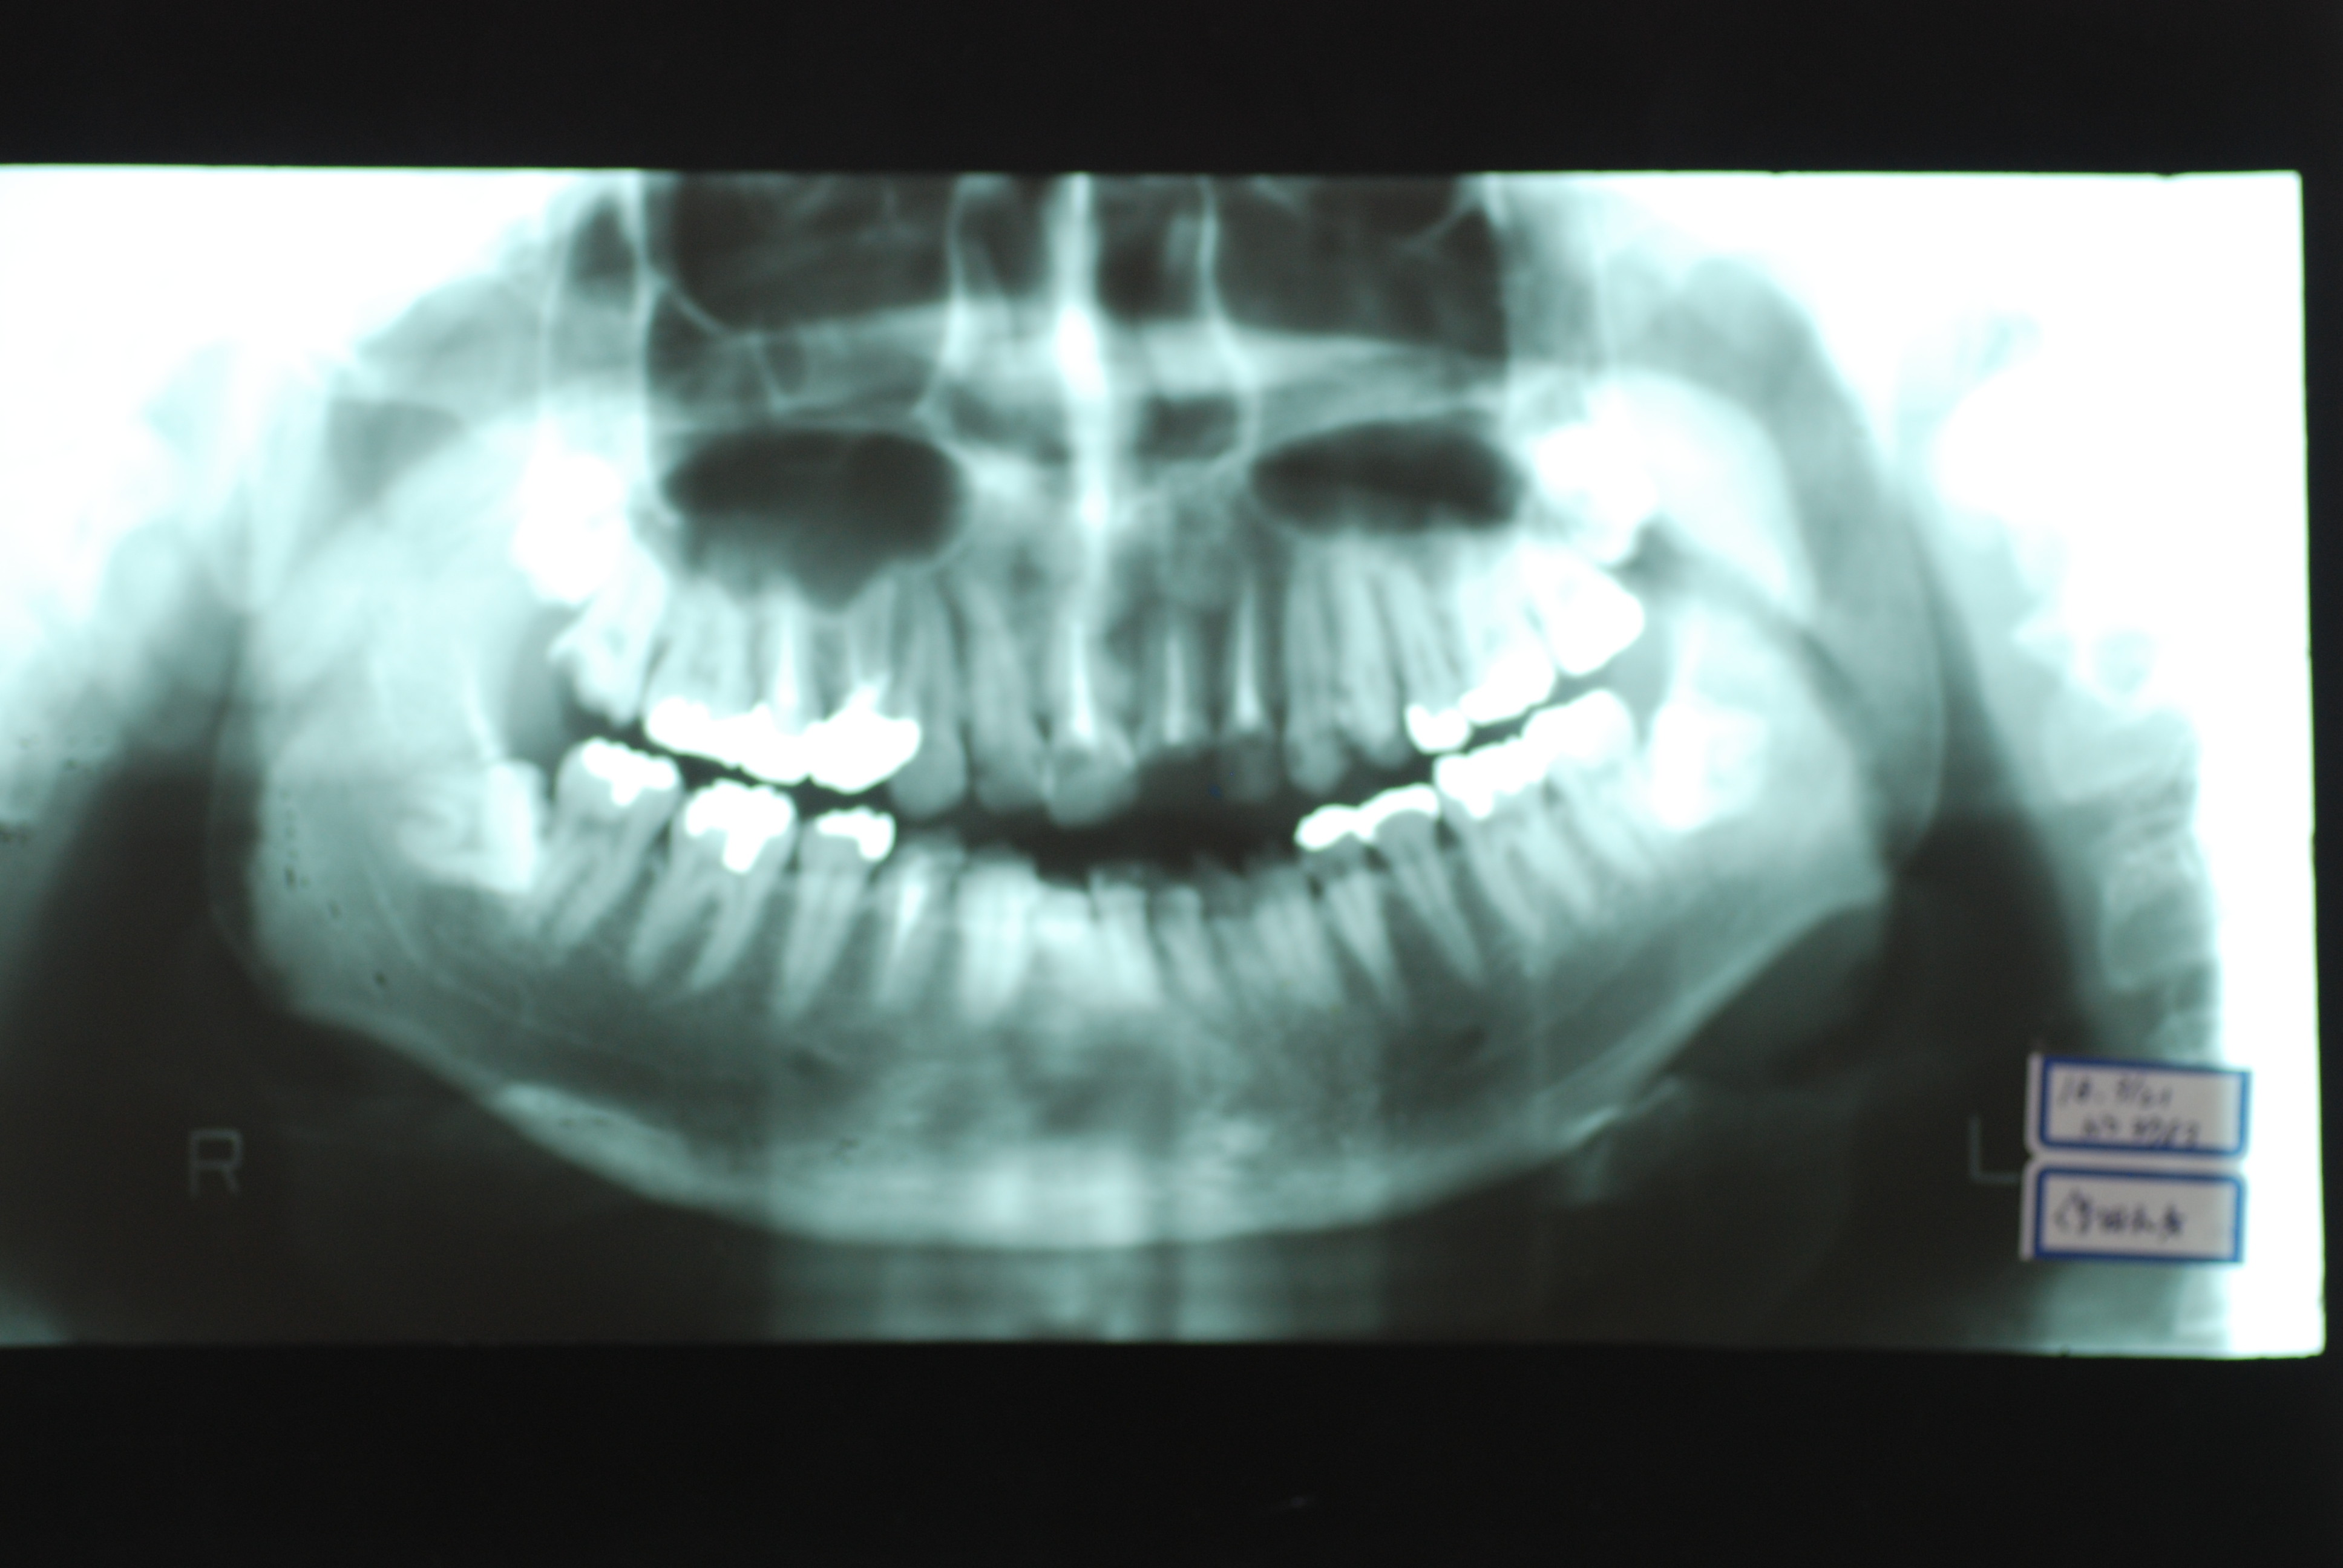

下の写真の方は虫歯と歯の間の歯周病が酷かったのです。

虫歯の治療も完全にできませんし、歯の位置が悪く又重なっている為に歯周病が治らずに説得に数カ月を有した後に矯正することになりました。

矯正治療一ヶ月後です。歯並びのガタガタはすぐよくなっています。